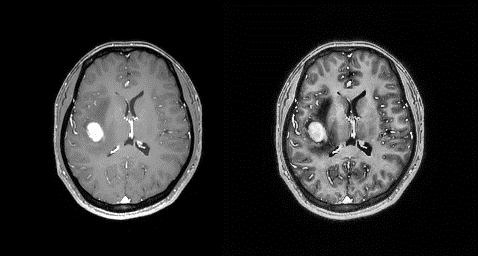

Figure 2. Original contrast enhanced T1-weighted SE

image (left) and AHE processed (right) with sliding window size=10 and

Clip factor=300